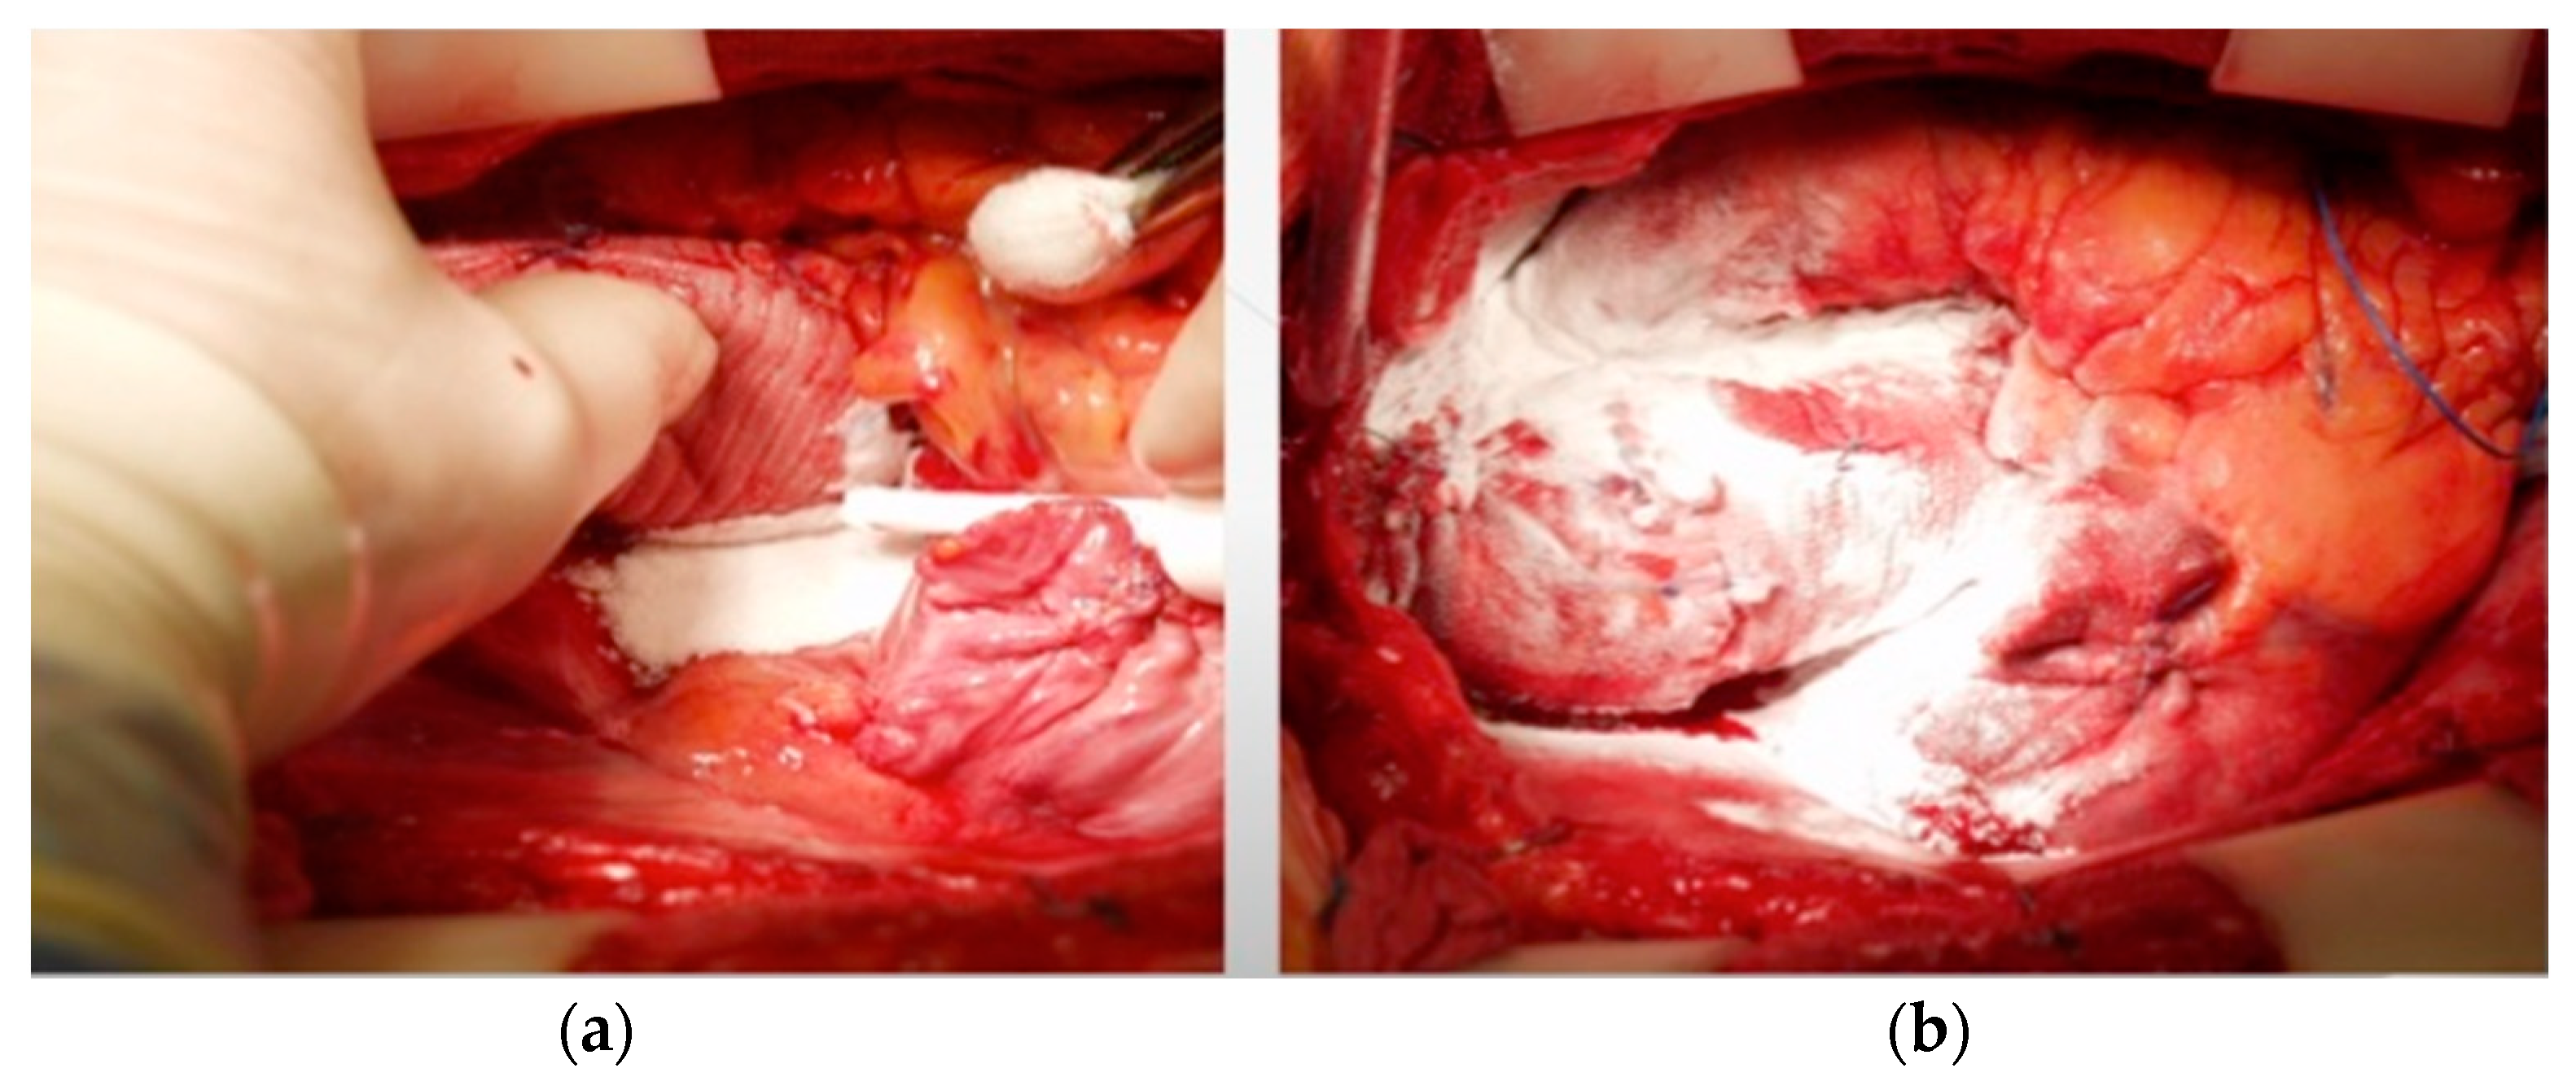

2.2. Surgical Technique

2.3. Study Product